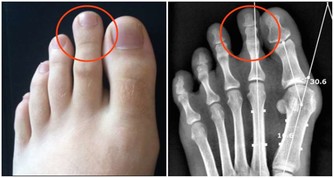

二、維生素B

維生素B存在很多種,一般統稱為維生素B族,這可物質能夠讓人體的骨骼更加強壯,還能幫助促進人體新陳代謝。而當人體缺乏維生素B時,就可能引發多種疾病。

其中,缺乏維生素B1,容易引起消化不良、厭食、大便乾燥等症狀,嚴重的還會導致嘔吐、四肢浮腫等;